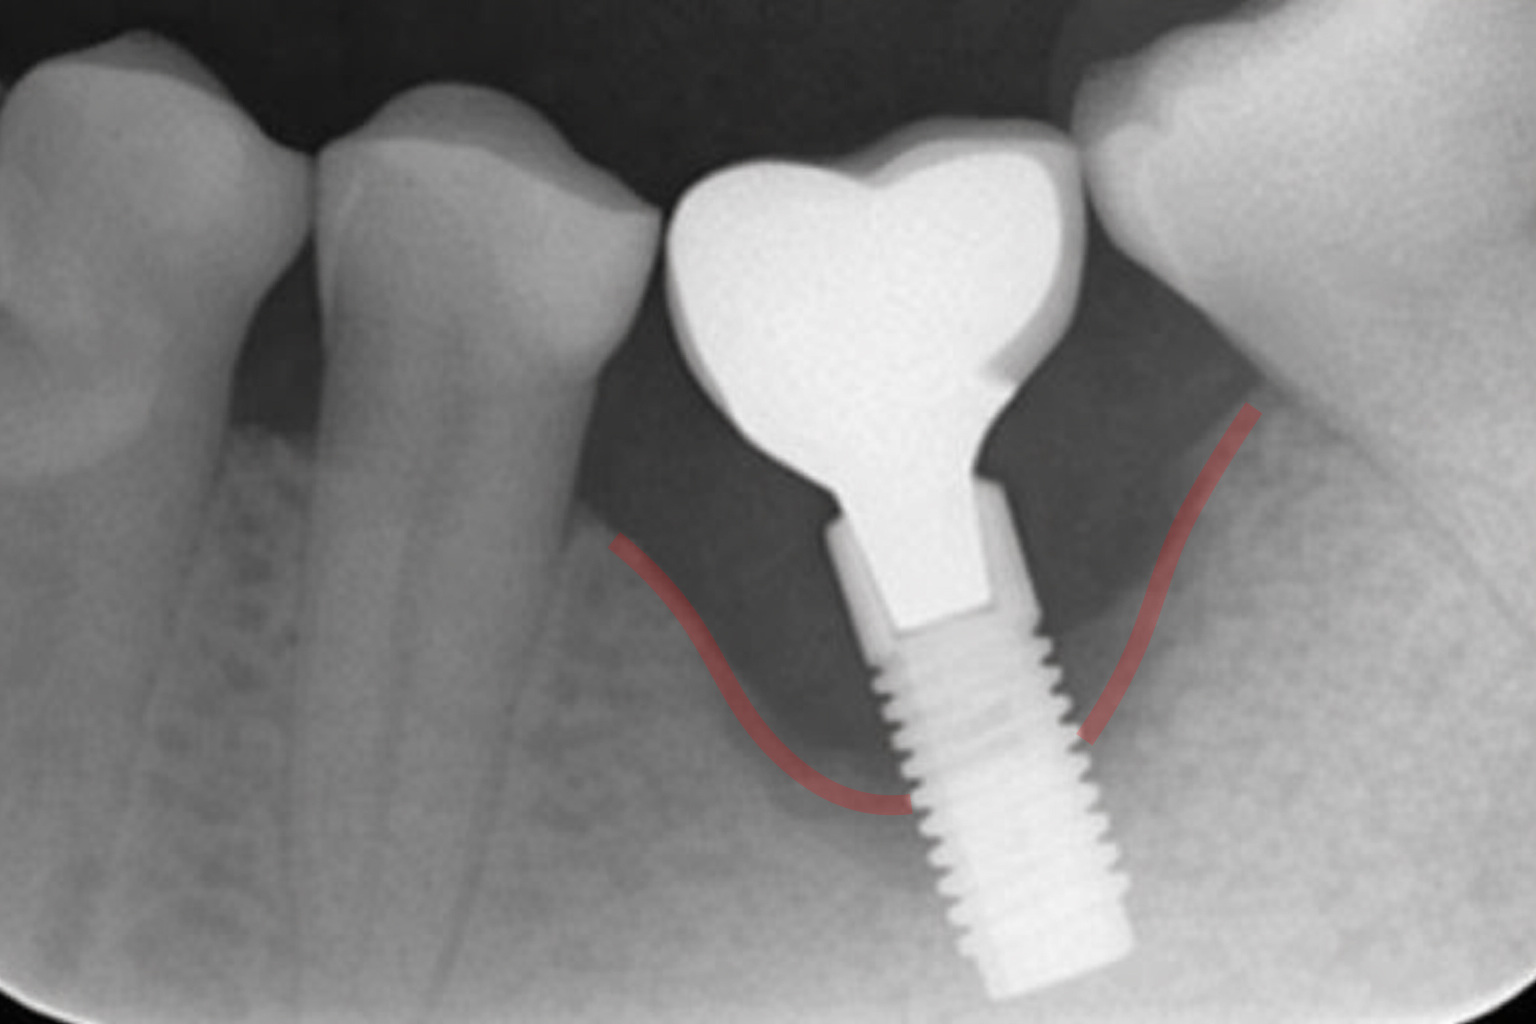

자연치아와 임플란트의 가장 큰 차이점은 ‘신경’의 유무입니다. 자연치아는 염증이 생기면 시리거나 아픈 신호를 보내지만, 임플란트는 신경이 없어 잇몸뼈가 녹아내려도 환자 본인이 자각하기 어렵습니다.

많은 분들이 임플란트를 제2의 치아라고 생각하시며 안심하시지만, 사실 임플란트는 자연치아보다 세균 침투에 더 취약한 구조를 가지고 있습니다. 이것이 바로 우리가 ‘임플란트 주위염’을 경계해야 하는 결정적인 이유입니다.

임플란트는 잇몸뼈에 직접 유착되어 있기 때문에 흔들린다는 것은 이미 지지하고 있는 잇몸뼈의 손실이 상당히 진행되었음을 의미합니다. 만약 손가락이나 혀로 건드렸을 때 보철물이 흔들리는 느낌이 들거나, 음식을 씹을 때 위치가 어긋나는 듯한 이물감이 느껴진다면 이는 지지 기반인 잇몸뼈가 상당 부분 소실되었음을 의미합니다. 뼈가 녹아내려 고정력이 약해진 상태에서는 기존 임플란트를 제거하고 뼈 이식 후 재수술을 해야 하는 상황으로 이어질 가능성이 높아집니다.